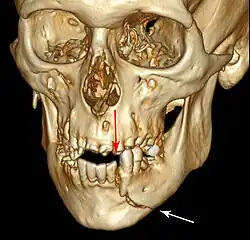

3D computed tomographic image of a mandible fracture in two places. One is a displaced right angle fracture and the other is a left parasymphyseal fracture.

Computed tomography

Computed tomography is the most sensitive and specific of the imaging techniques. The facial bones can be visualized as slices through the skeletal in either the axial, coronal or sagittal planes. Images can be reconstructed into a 3-dimensional view, to give a better sense of the displacement of various fragments. 3D reconstruction, however, can mask smaller fractures owing to volume averaging, scatter artifact and surrounding structures simply blocking the view of underlying areas.

multiple mandible fractures of a patient in the right condyle (extracapsular/neck/not dislocated), right body (vertically unfavourable) and left coronoid process